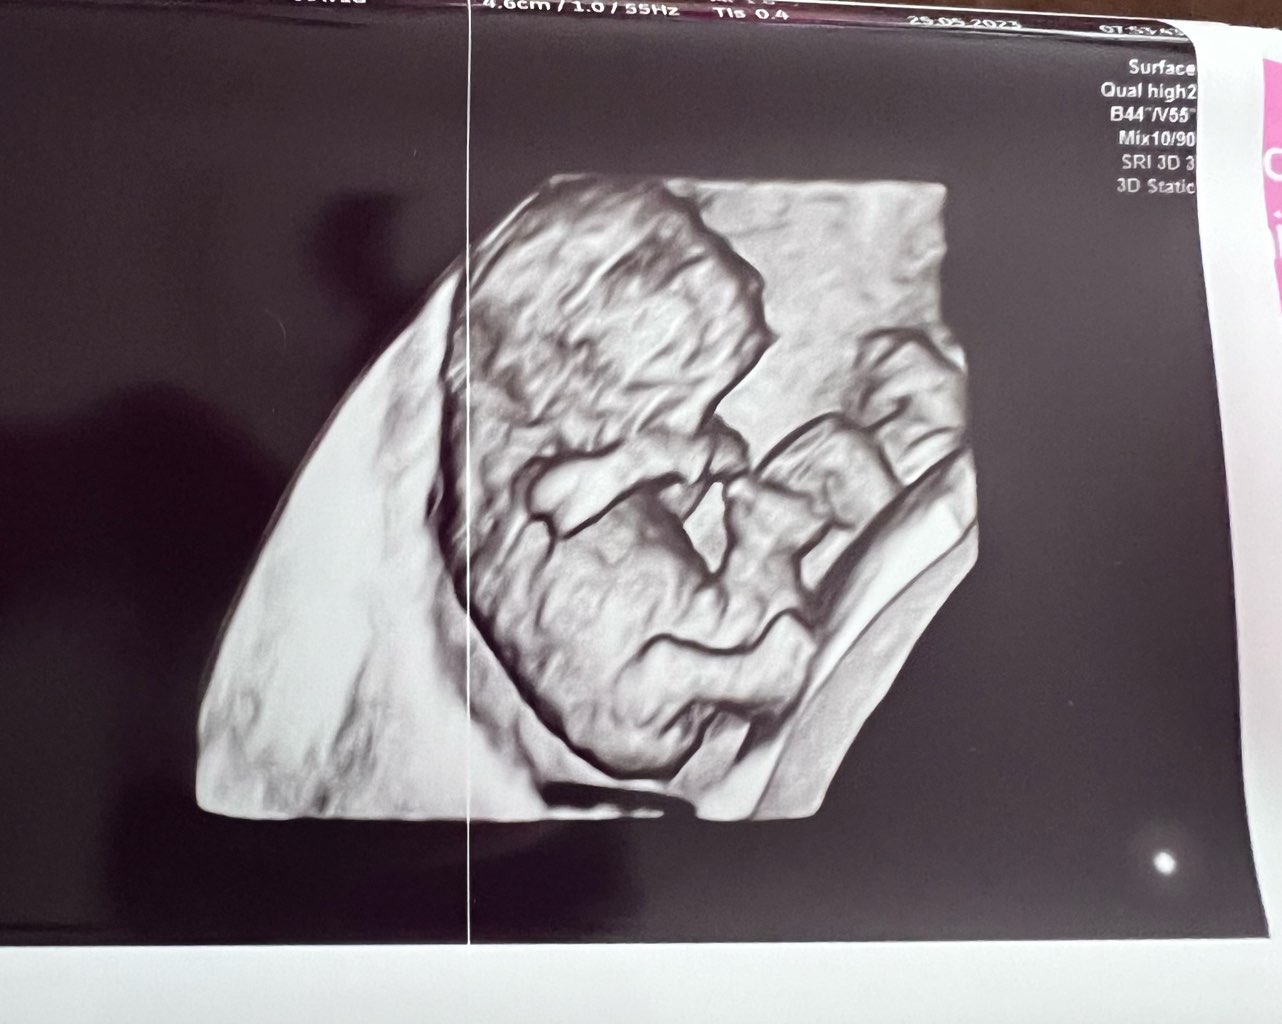

Dzień doberek! Jak tam się czujecie? Ja po wizycie i wyglądamy teraz tak. Prenatalne umówione na 14.06

• IMG_6030.jpeg

IMG_6030.jpeg

170,6 KB · Wyświetleń: 136